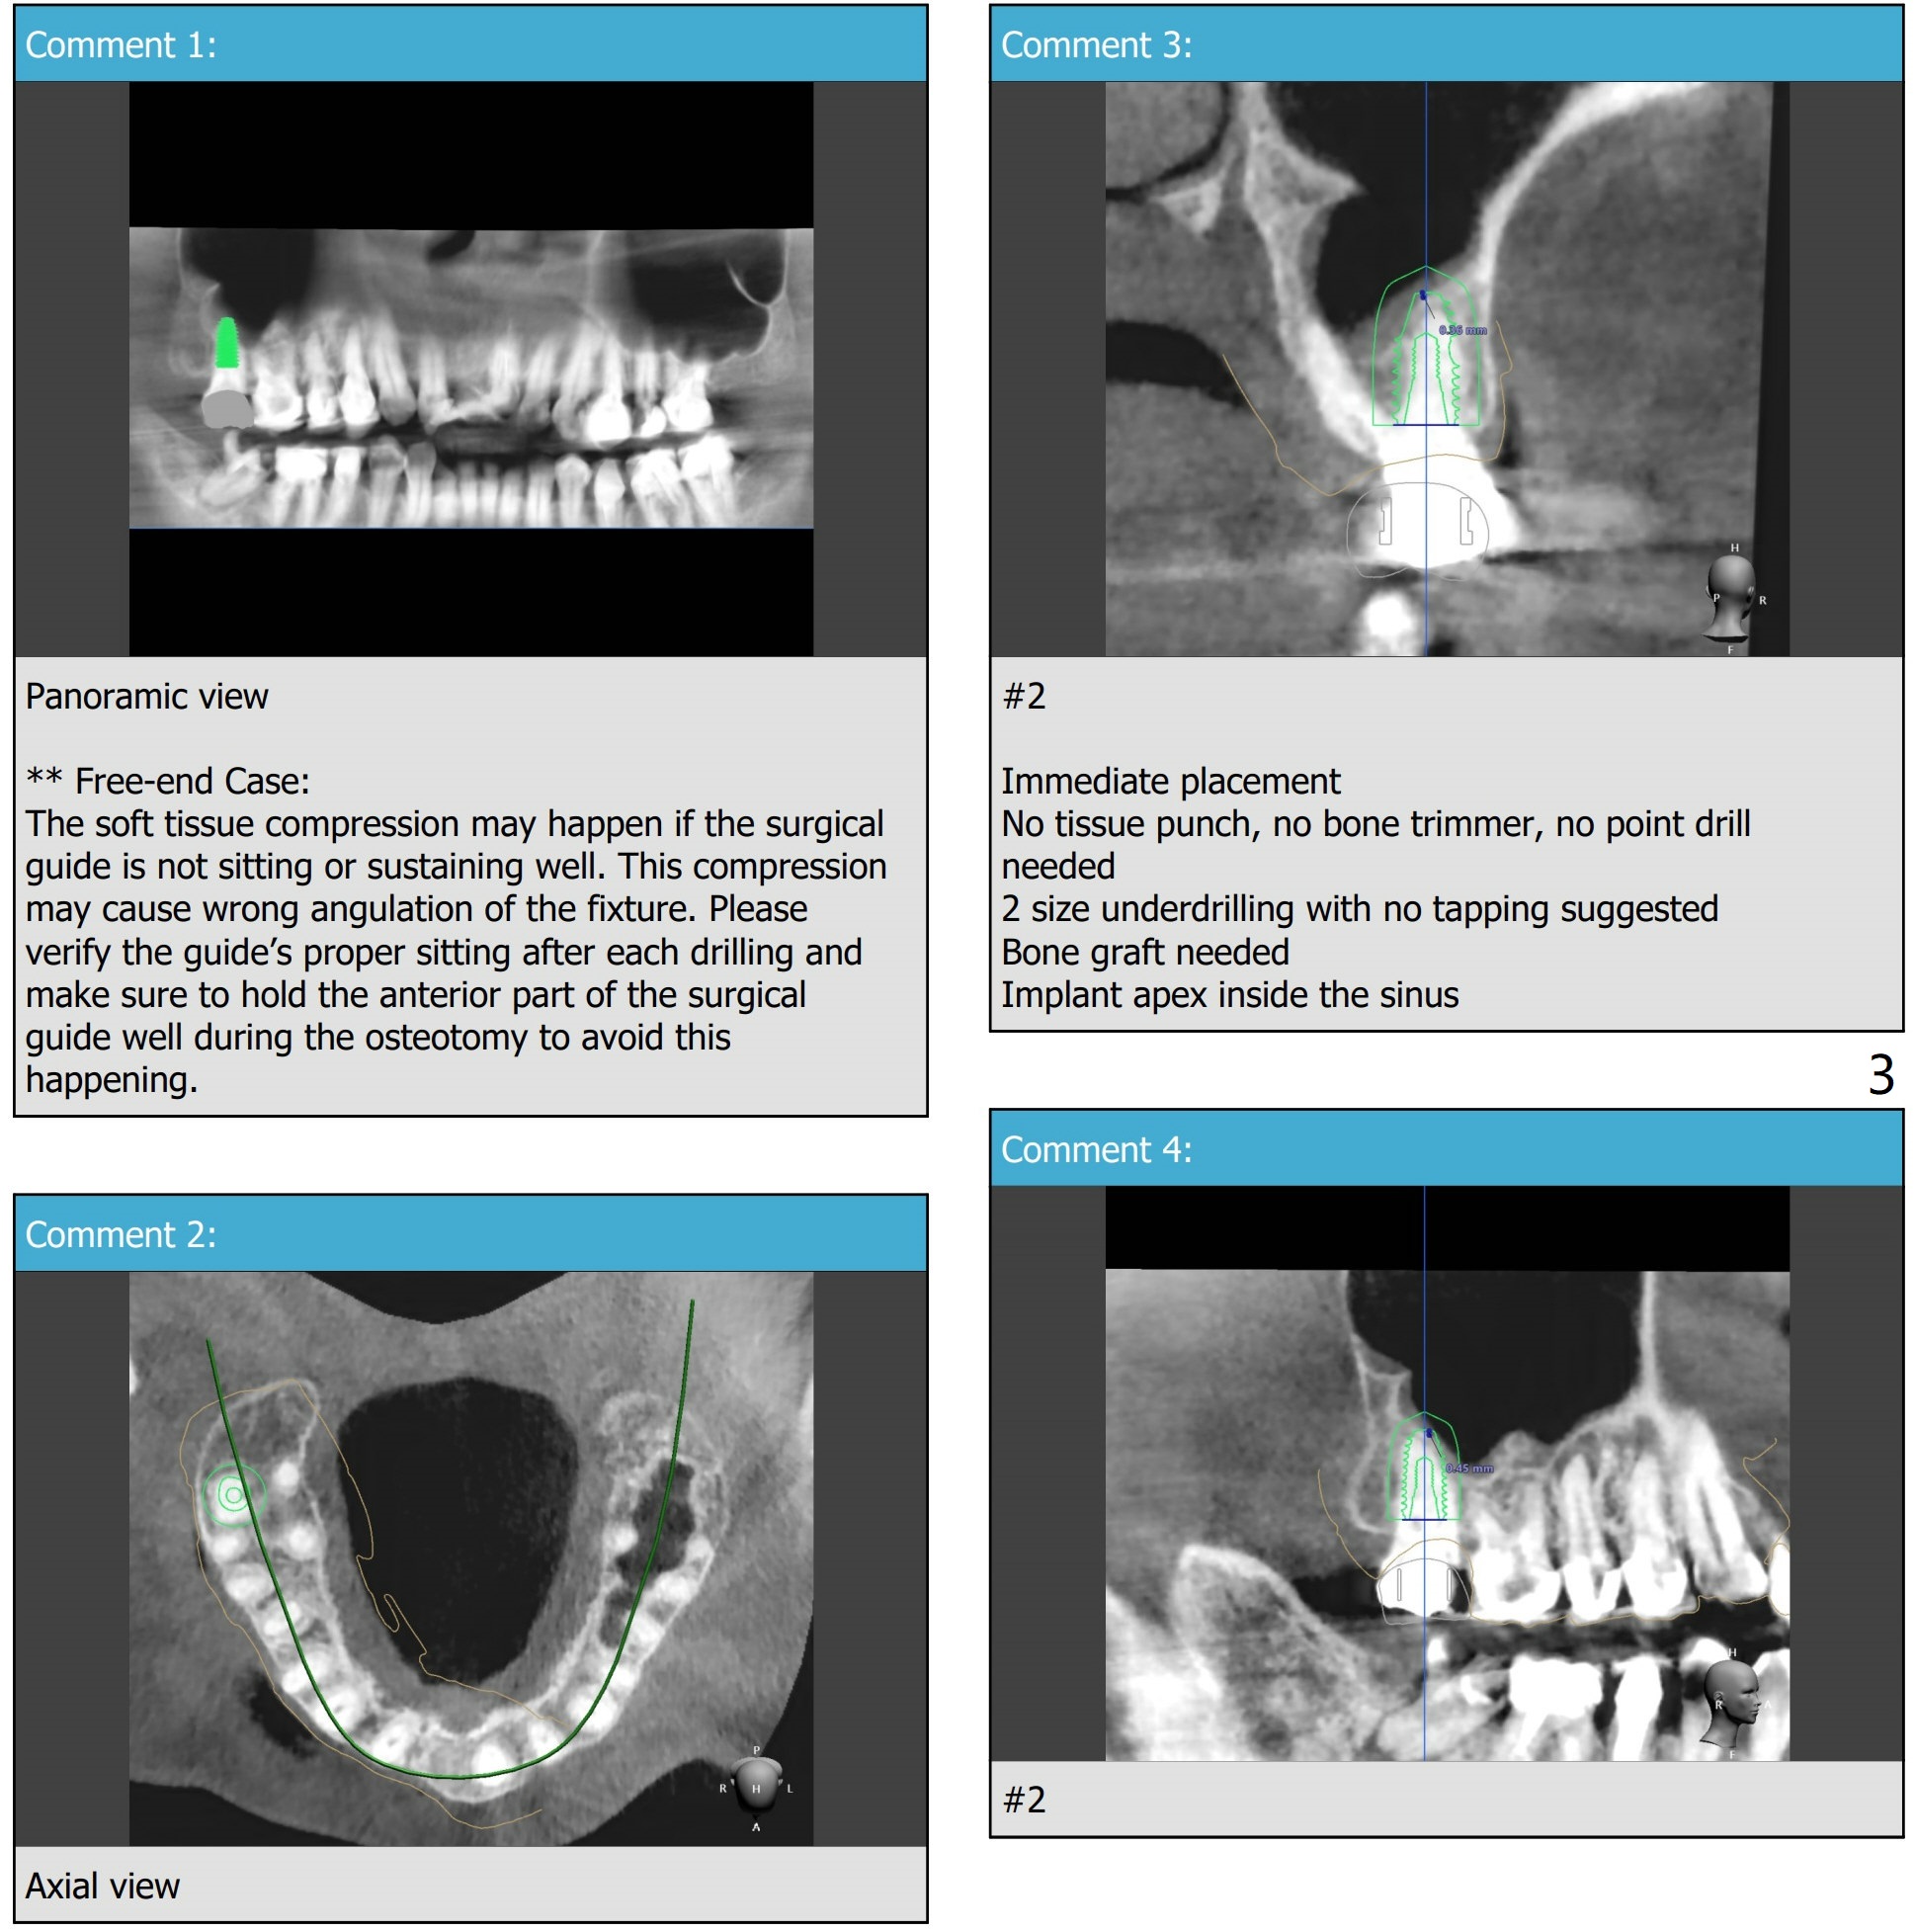

Mandatory Sinus Lift for #2

Return to Protect Graft